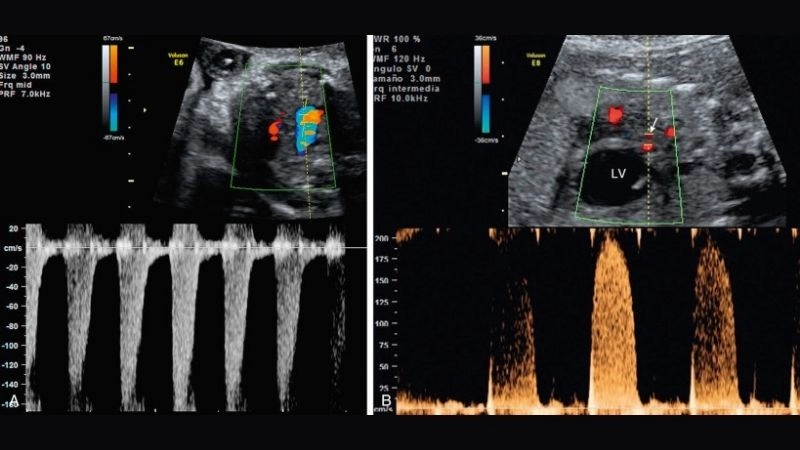

Images visual examples of aortic valve atresia

Aortic valve atresia is a rare congenital heart defect where the aortic valve fails to form correctly, blocking blood flow from the heart to the body.